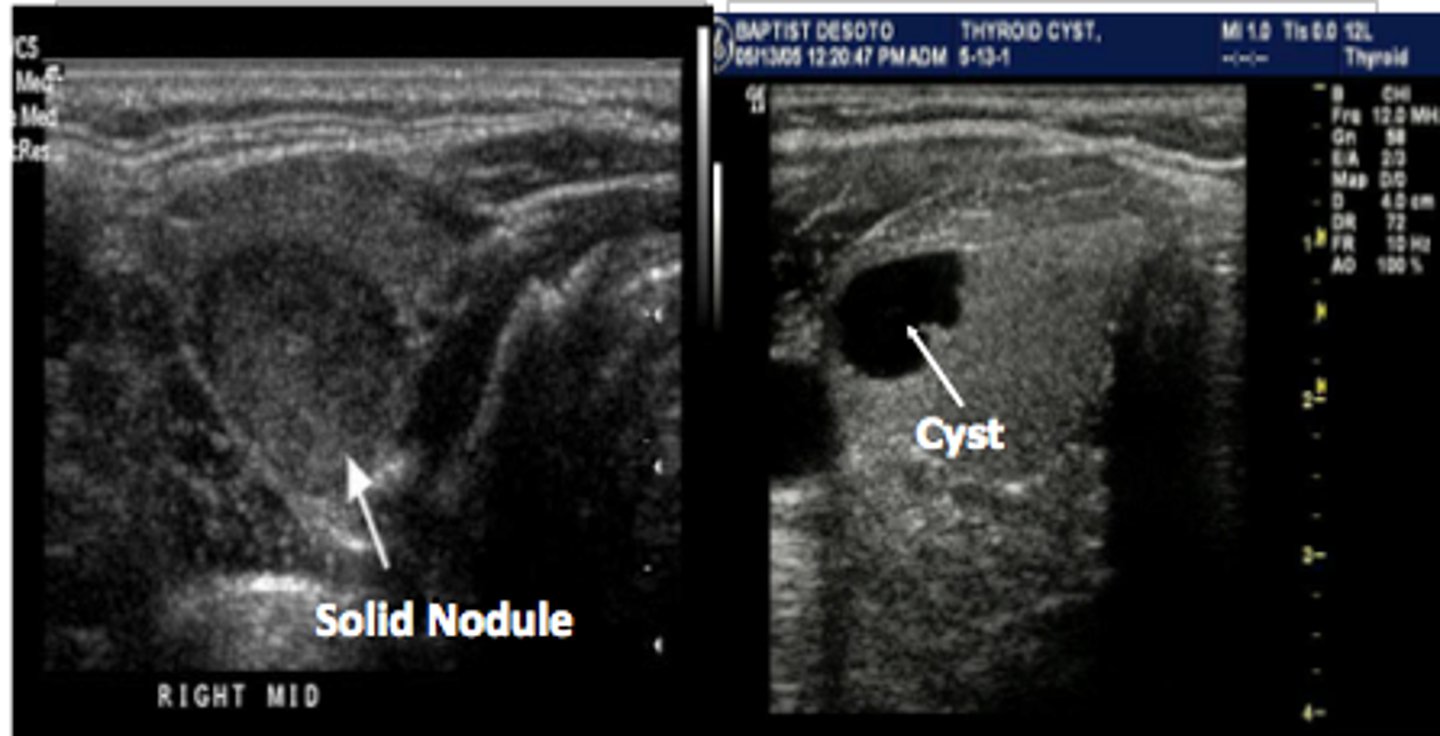

Benign Thyroid Neoplasms - Cyst:

10-15% of solitary thyroid nodules

Etiology

-Simple cyst

Clinical findings

-Asymptomatic

-Palpable neck mass

Sonographicfindings

-Anechoic mass

-Smooth wall margins

-Posterior acoustic enhancement

-May demonstrate internal debris

Benign Thyroid Neoplasms - Adenoma:

Sonographic findings

-Homogeneous _____ mass

-Prominent _____echoic peripheral halo

-_____ blood flow

-May degenerate and appear _____

-"_____" nodule on nuclear medicine scan

-Composed of epithelial tissue

-Most common thyroid neoplasm

-Hyperthyroidism

-Female prevalence (7:1)

-Homogeneous echogenic mass

-Prominent hypoechoic peripheral halo

-Peripheral blood flow

-May degenerate and appear complex

-"Cold" nodule on nuclear medicine scan